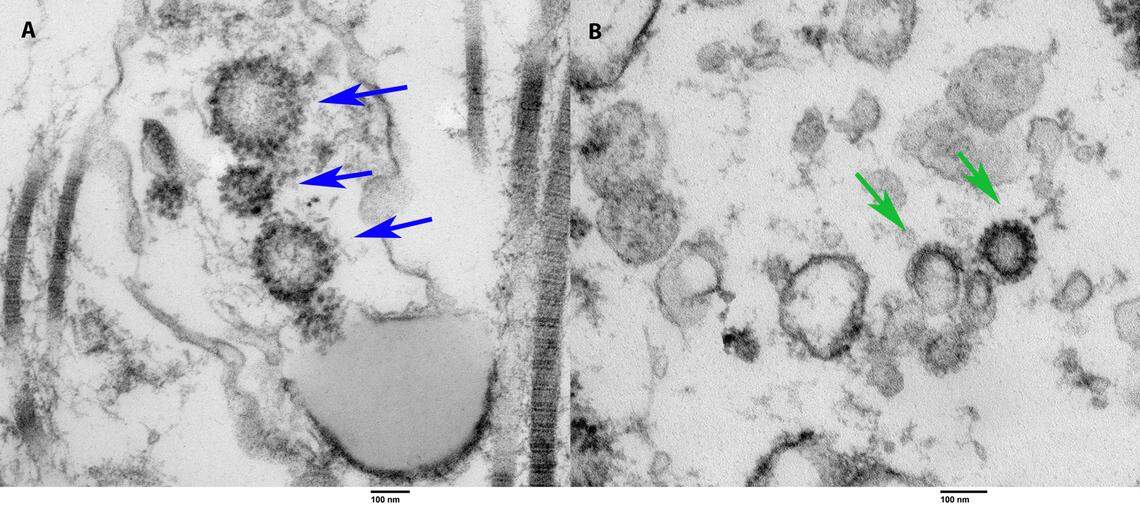

COVID-19 viral particles found via electron microscopy. On the left is tissue taken from a live, previously COVID-positive patient. On the right is tissue collected via autopsy from a person who died of COVID-19. The arrows point toward the spiked COVID viral particles in both specimens, according to a study by University of Miami doctors.

COVID-19 viral particles found via electron microscopy. On the left is tissue taken from a live, previously COVID-positive patient. On the right is tissue collected via autopsy from a person who died of COVID-19. The arrows point toward the spiked COVID viral particles in both specimens, according to a study by University of Miami doctors. University of Miami

Ramasamy and eight colleagues analyzed testis tissue from the autopsies of six men who died of COVID-19 infection in Miami-Dade County. They found impaired sperm function in three of the testis specimens and evidence of COVID-19 using electron microscopy in the tissue of one.

“We also identified the presence of the virus in a man who underwent a testis biopsy for infertility but had a previous history of COVID-19. So the patient tested negative and was asymptomatic after having COVID-19 but still showed the presence of the virus inside the testes,” Ramasamy said in a statement.